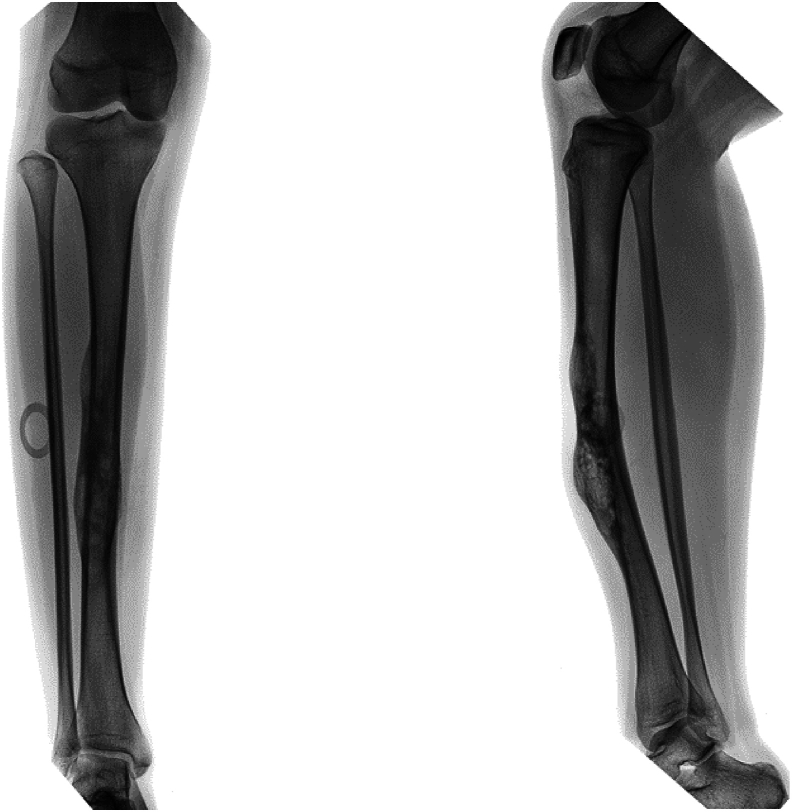

A 12+9-year-old female-assigned at birth diagnosed with osteofibrous dysplasia of her right tibia underwent 15cm bone resection, ipsilateral pedicled fibular graft, and frame application without a thorough multidisciplinary preoperative evaluation. During her course of treatment, the patient's mood and ability to participate in her own care (e.g. showering, feeding herself on a regular and consistent basis, completing home exercises) declined precipitously, and she began to endorse symptoms of suicidal ideation and non-suicidal self-injury behavior. Eventually the patient had to be admitted to the team's pediatric orthopaedic institution and was later transferred to an intensive outpatient mental health program for safety and mood stabilization. Due to multiple absences, the patient was prematurely dismissed from the mental health program and subsequently refused to participate with any sort of mental health intervention. Simultaneously, she struggled to cope with the demands of her external fixation treatment.Broadly, this case highlights the critical importance of thorough psychological assessment prior to consideration of limb lengthening and/or reconstruction. Psychological assessment should first establish the patient's baseline mental health, identify any extant mental health symptoms, and connect the patient with appropriate intervention as needed. Second, psychological assessment should establish the family's baseline functioning, including caregiver availability and support as well as emotional and logistical resources available to support treatment. Third, psychological assessment should continue throughout the course of treatment, in order to identify real time possible changes in a patient's mental health and intervention needs.

一名12+9岁女性,出生时被诊断为右胫骨骨纤维性发育不良,在没有进行全面的多学科术前评估的情况下,接受了15cm骨切除、同侧带蒂腓骨移植和框架应用。在治疗过程中,患者的情绪和参与自我护理的能力(如洗澡、定期和持续地自己进食、完成家庭运动)急剧下降,并开始出现自杀意念和非自杀自残行为的症状。最终,患者不得不住进该团队的儿科骨科机构,随后被转移到一个强化的门诊心理健康项目,以确保安全和情绪稳定。由于多次缺席,患者被过早地从心理健康项目中解雇,随后拒绝参加任何形式的心理健康干预。同时,她也在努力应对外固定治疗的要求。总的来说,这个病例强调了在考虑肢体延长和/或重建之前进行彻底的心理评估的重要性。心理评估应首先确定患者的心理健康基线,确定任何现存的心理健康症状,并根据需要将患者与适当的干预联系起来。第二,心理评估应该建立家庭的基本功能,包括照顾者的可用性和支持,以及支持治疗的情感和后勤资源。第三,心理评估应在整个治疗过程中持续进行,以便实时识别患者心理健康和干预需求的可能变化。关键概念:(2)术前心理评估应建立患者的基线心理健康状况,并确定任何先前存在的心理健康问题。(3)术前心理评估应建立患者的家庭基线功能,重点关注认知、(4)心理评估应在整个治疗过程中持续进行,以便及时识别治疗过程中出现的任何情绪问题。